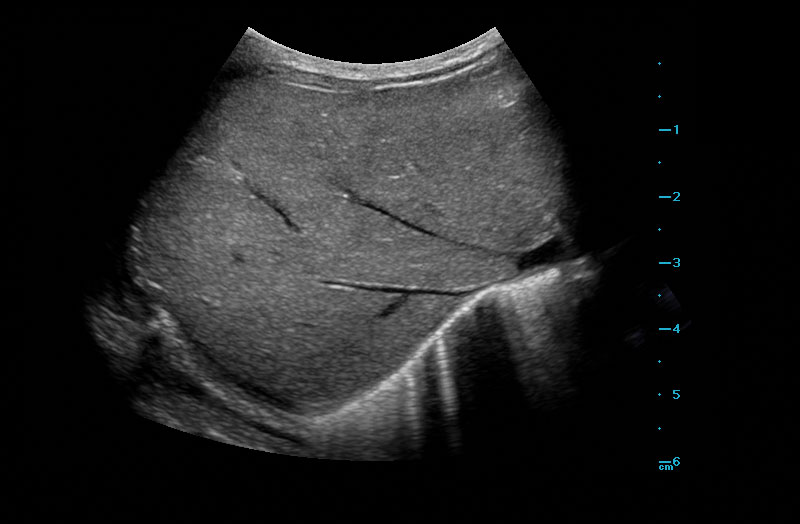

The Z.One PRO Ultrasound System Emerald Edition 2.0 is a powerful and portable advanced point-of-care imaging platform. Powered by software-based ZONE Sonography® Technology+ (ZST+), the Z.One PRO System provides optimal B-mode and Doppler imaging for patients, regardless of body habitus, helping ensure a reliable diagnosis. With a full family of transducers (from 2 – 20 MHz) and a wide range of applications, the Z.One PRO System is the imaging answer to your difficult clinical cases.

Advanced needle visualization technology allows increased needle visibility even during steep-angled procedures, while maintaining superior image quality. Improved confirmation of needle location in tissue minimizes harm to surrounding tissue.